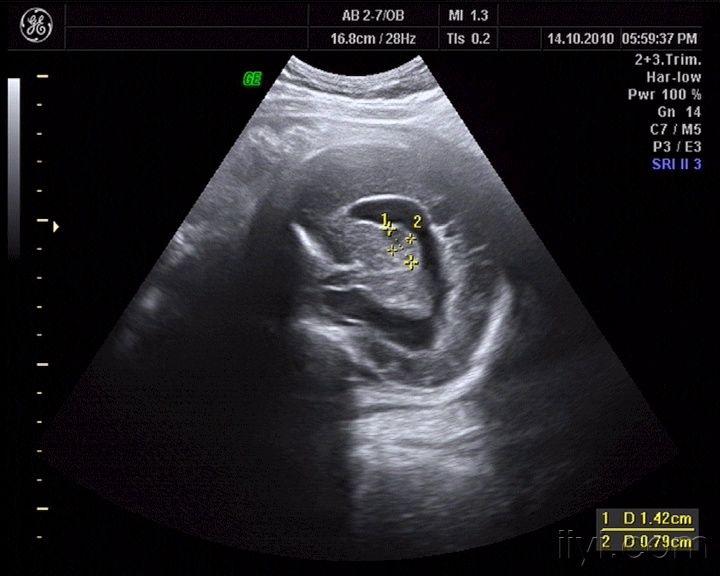

胎儿颅内结构超声切面

胎儿颅内结构超声切面,胎儿脑部超声切面图解

看看这个胎儿颅内情况,见过没有,考虑什么啊 - 超声版

胎儿超声标准切面详解

胎儿双顶径切面图解

胎儿丘脑水平切面图解

丘脑水平横切面超声图